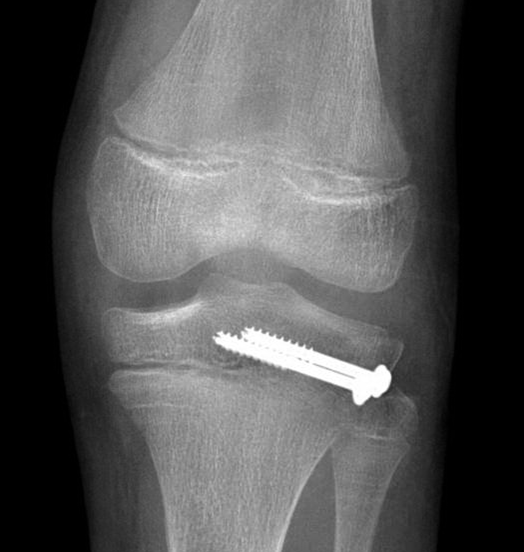

Age: 11

Sex: Male

Indication: Knee pain

Sample ReportAcute nondisplaced, nondepressed fracture of the lateral tibial plateau with extension into the physis (Salter III). Surrounding soft tissue swelling.

Large joint effusion.

No joint malalignment.